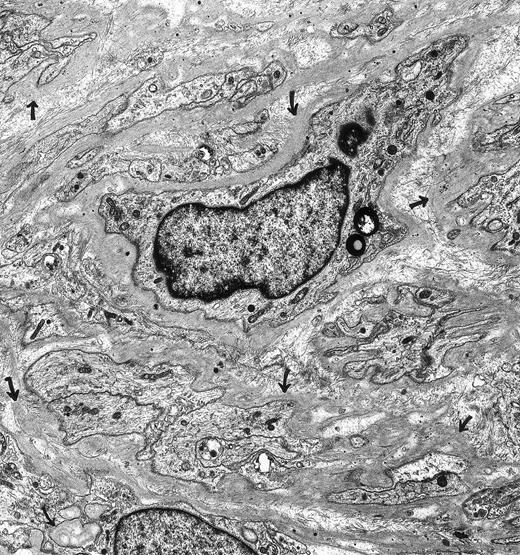

Schwannoma. A 66-year-oldman had a nonenlarging retroperitoneal mass for 3 years that was composed of Schwann cells. The spindle cells and their extensive, narrow cellular processes were encased in basal lamina (arrows). The tumor cells lacked surface vesicles, bundles of microfilaments, dense bodies and dense surface plaques—features characteristic for tumors of smooth muscle cell origin. Immunoperoxidase stains were positive for vimentin and S-100 and negative for muscle-specific actin. Original magnification × 7,500. (Courtesy of Ann M. Dvorak, MD, Department of Pathology, Beth Israel Deaconess Medical Center, 330 Brookline Ave, Boston, MA 02215.)